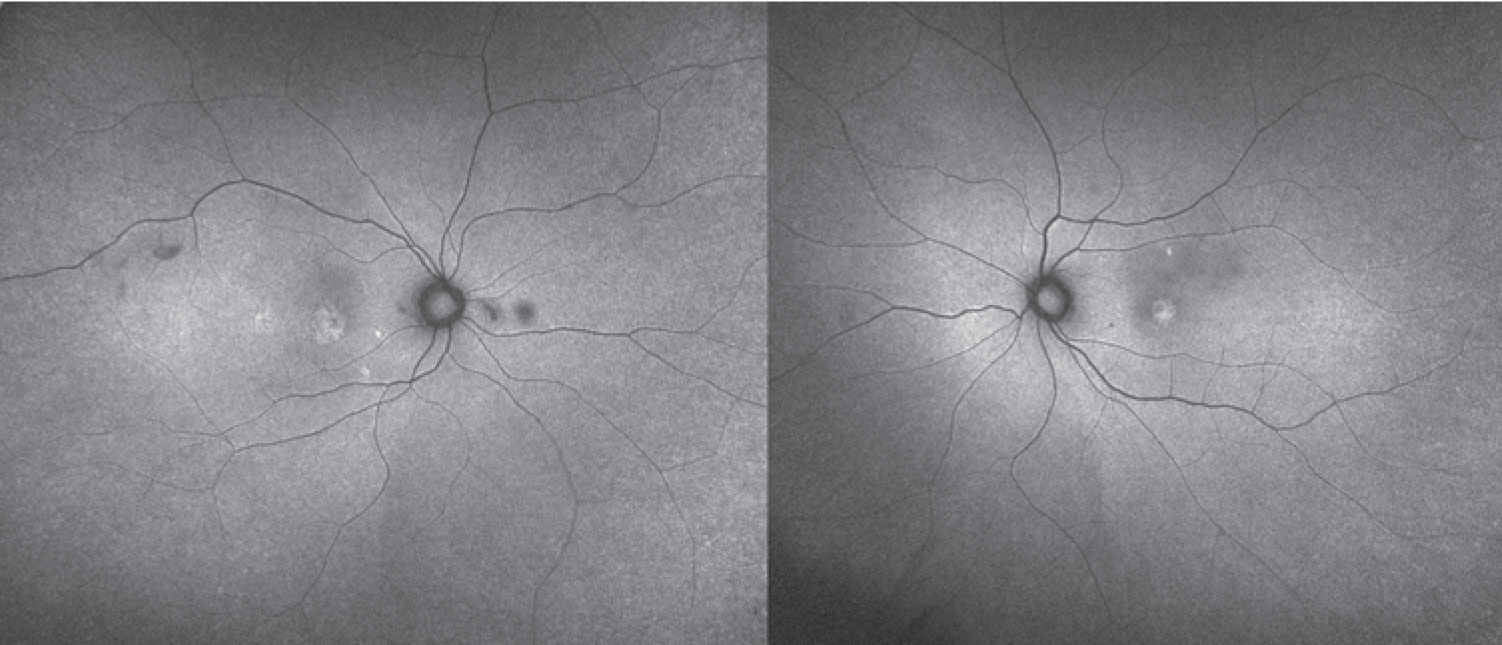

Given the ophthalmoscopic exam, we pursued further diagnostic imaging. Fundus autofluorescence revealed bilateral areas of hyperautofluorescence that correlated to the accumulation of SRF. We observed no foci of hyperautofluorescence in the periphery. Absent were gravity-dependent fluid shifts, or guttering (Figure 3).

Figure 3. Fundus autofluorescence shows hyperautofluorescence corresponding to areas of subretinal fluid. |

MEKAR has been termed CSR-like, but there are important differences between these two conditions. MEKAR is bilateral more than 90 percent of the time, while CSR is bilateral in less than half.14 MEKAR is also frequently multifocal, involves the posterior pole at the fovea and along the arcades, and has no gravitational effect on the fluid as is seen in CSR.14 Furthermore, the pigment epithelial detachments and increased choroidal thickness commonly observed in CSR don’t necessarily occur in MEKAR.14